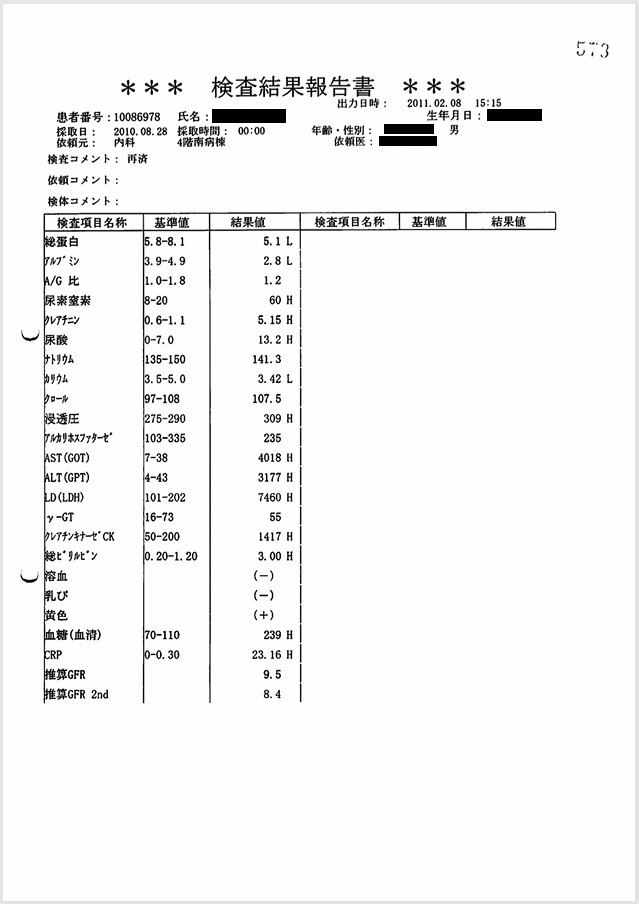

- 8月24日~8月31日:重度のショック肝・ショック腎

ショック肝(重症肝不全:ピーク値:AST 4018 U/l, ALT 3177 U/l)、ショック腎(重症腎不全:Cre 5.15 mg/dl)の進行。ショック解除後、悪化なし。

証拠:血液検査データ

入院した8月25日から8月28日にかけて血液検査で肝機能の値(AST, ALT)、腎機能の値(Cre)が急激に上昇し、肝機能の値のピーク値は8月28日のAST 4018 U/l, ALT 3177 U/lと重度の肝不全であり、経過からはショック肝と考えられる。 また腎機能を示すCreは、8月26日にCre 0.82 mg/dl, 8月27日にCre 2.66 mg/dl, 8月28日にCre 5.15 mg/dlと腎不全が日単位で急激に進行しており、血圧低下の経過と一致しており、ショック腎と考えられる。

ショックの時間が長期化していたことから、ショック肝、ショック腎を初めとして、 全身臓器が傷害されて多臓器不全となり、回復不能の状態に陥った。